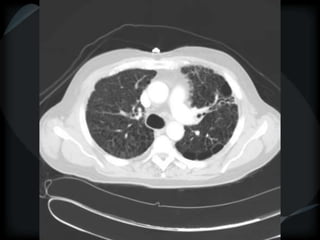

Dilated esophagus